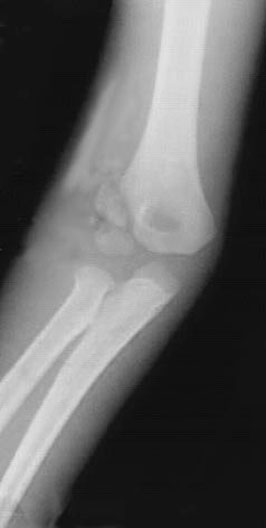

Elbow Dislocation

*Arrows point to dislocation